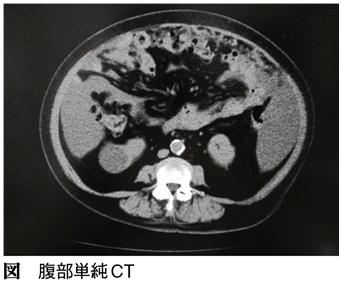

患者は79歳、女性。主訴は腹部膨満感です。2カ月ほど前から腹部膨満感があり、都内の某病院を受診されました。腹水の貯留が認められたため、精査入院となりました。腹部単純CT(図)では、腹水の貯留に加えて大網の肥厚がみられ、腹膜播種・癌性腹膜炎と診断されました。その後、腹水穿刺と細胞診の結果から腺癌と診断されました。腫瘍マーカーはCA125 1369U/mL、CEA 3.2ng/mLを示しており、原発巣を探すため上下部消化管内視鏡検査、乳腺エコー、マンモグラフィー検査が行われましたが、異常はありませんでした。さらに、婦人科と泌尿器科での診察も行われましたが、原発巣は特定されませんでした。